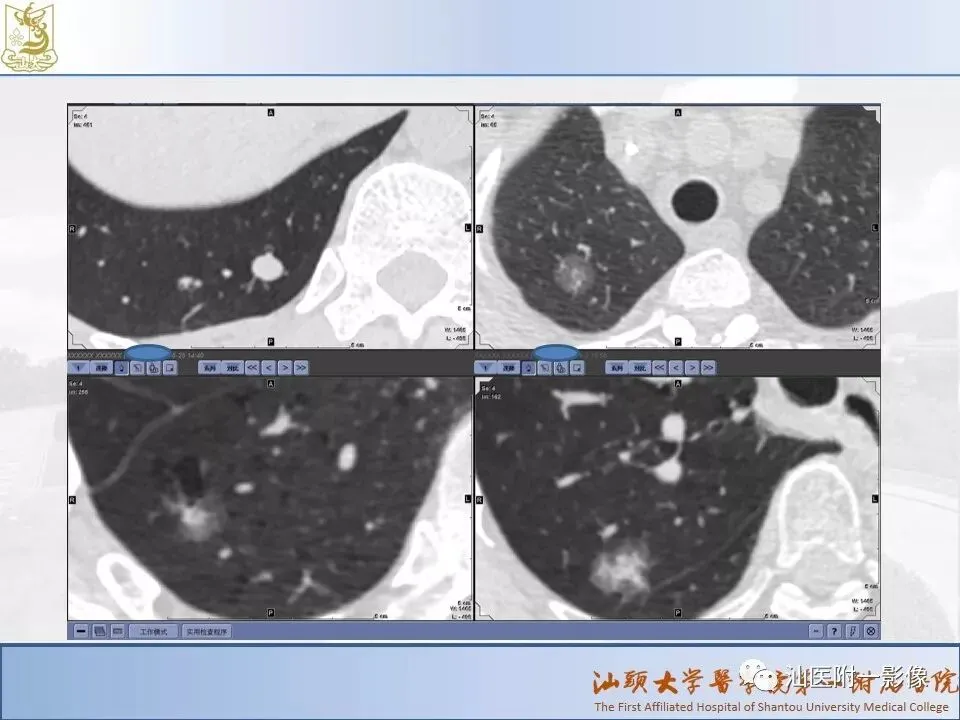

肺结节分类、处理及浅识肺结节分类影像报告和数据系统(Lung-RADS)

来源:汕医附一影像

说明:本课程病例主要来源于本院病例及参考资料,

无涉及病人隐私,仅做教学用途。